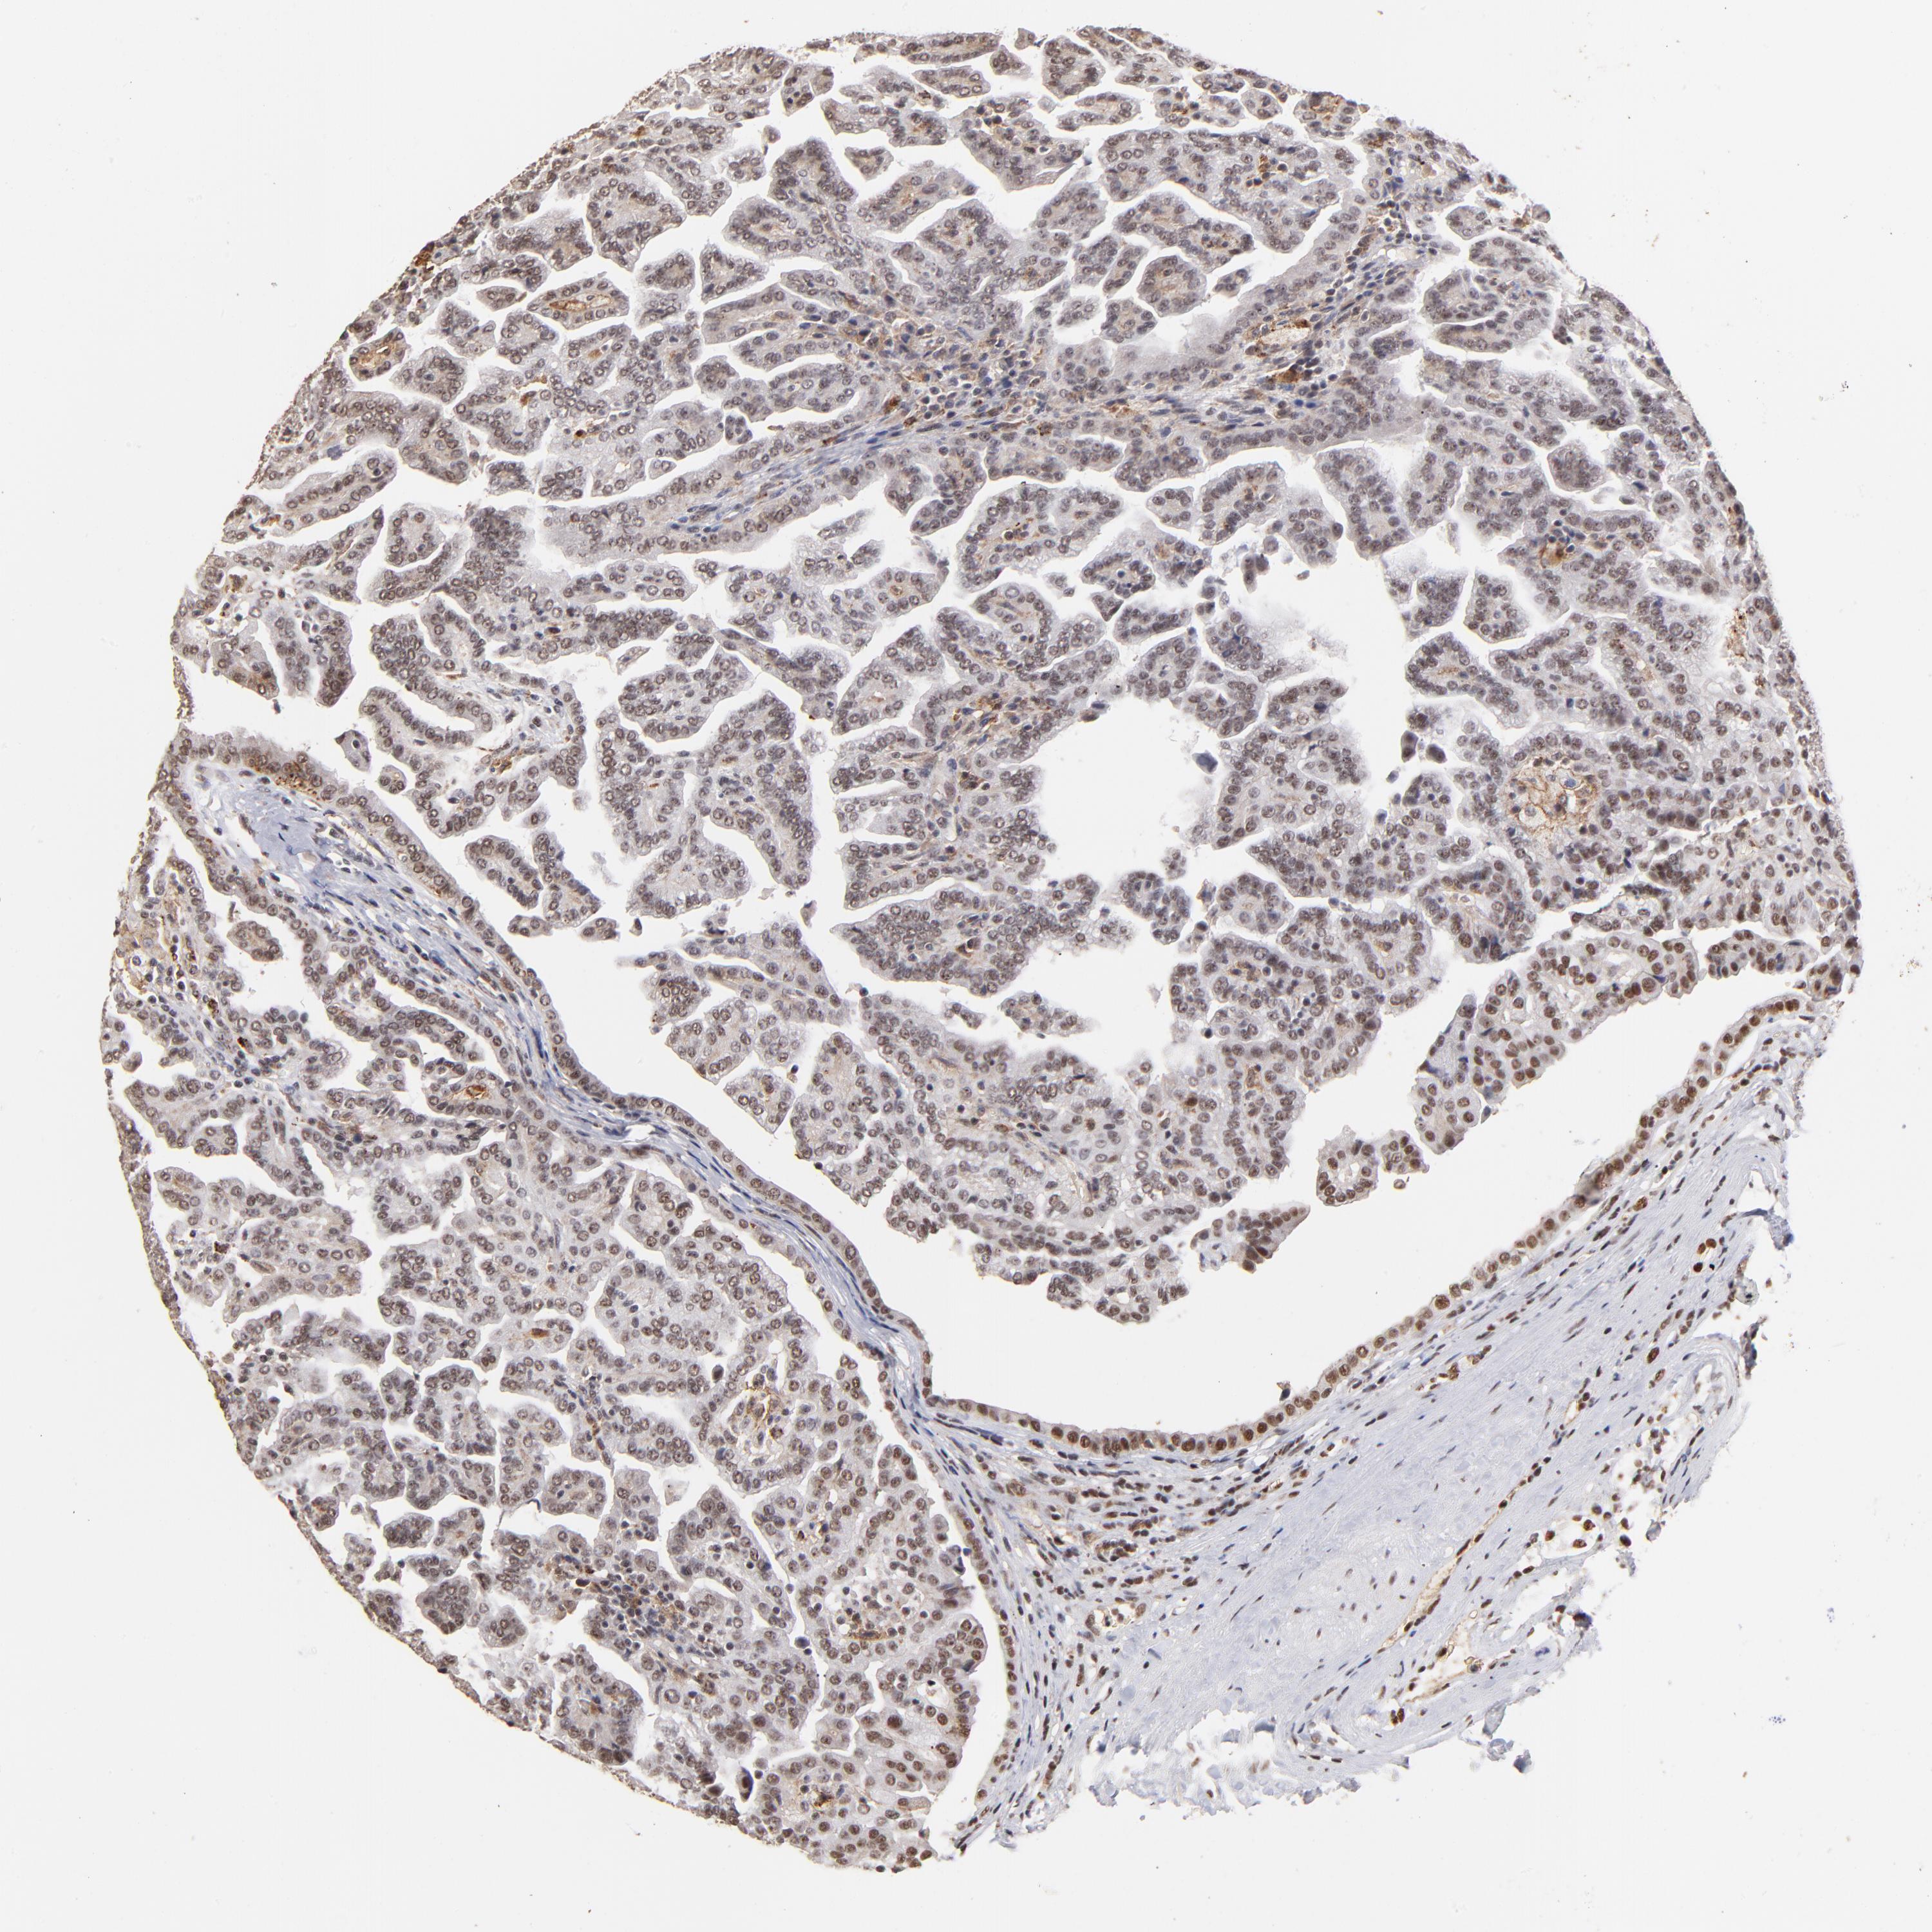

CANCER RENAL CANCER Show tissue menu

KICH TCGA KIRC TCGA KIRC VALIDATION KIRP TCGA PROTEIN RCC CPTAC PROTEIN EXPRESSION